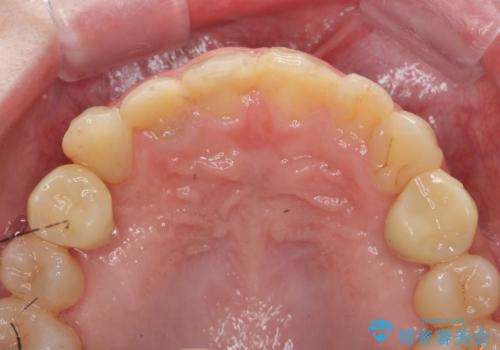

残根状態の歯、神経まで虫歯が達し失活した歯、歯肉縁下まで及んだ虫歯が多数認められます。

まず虫歯を拡大鏡、マイクロスコープ下で丁寧に取り除き歯肉縁下の虫歯を歯周外科により解決したのち、ジルコニアクラウン製作を行っていきます。